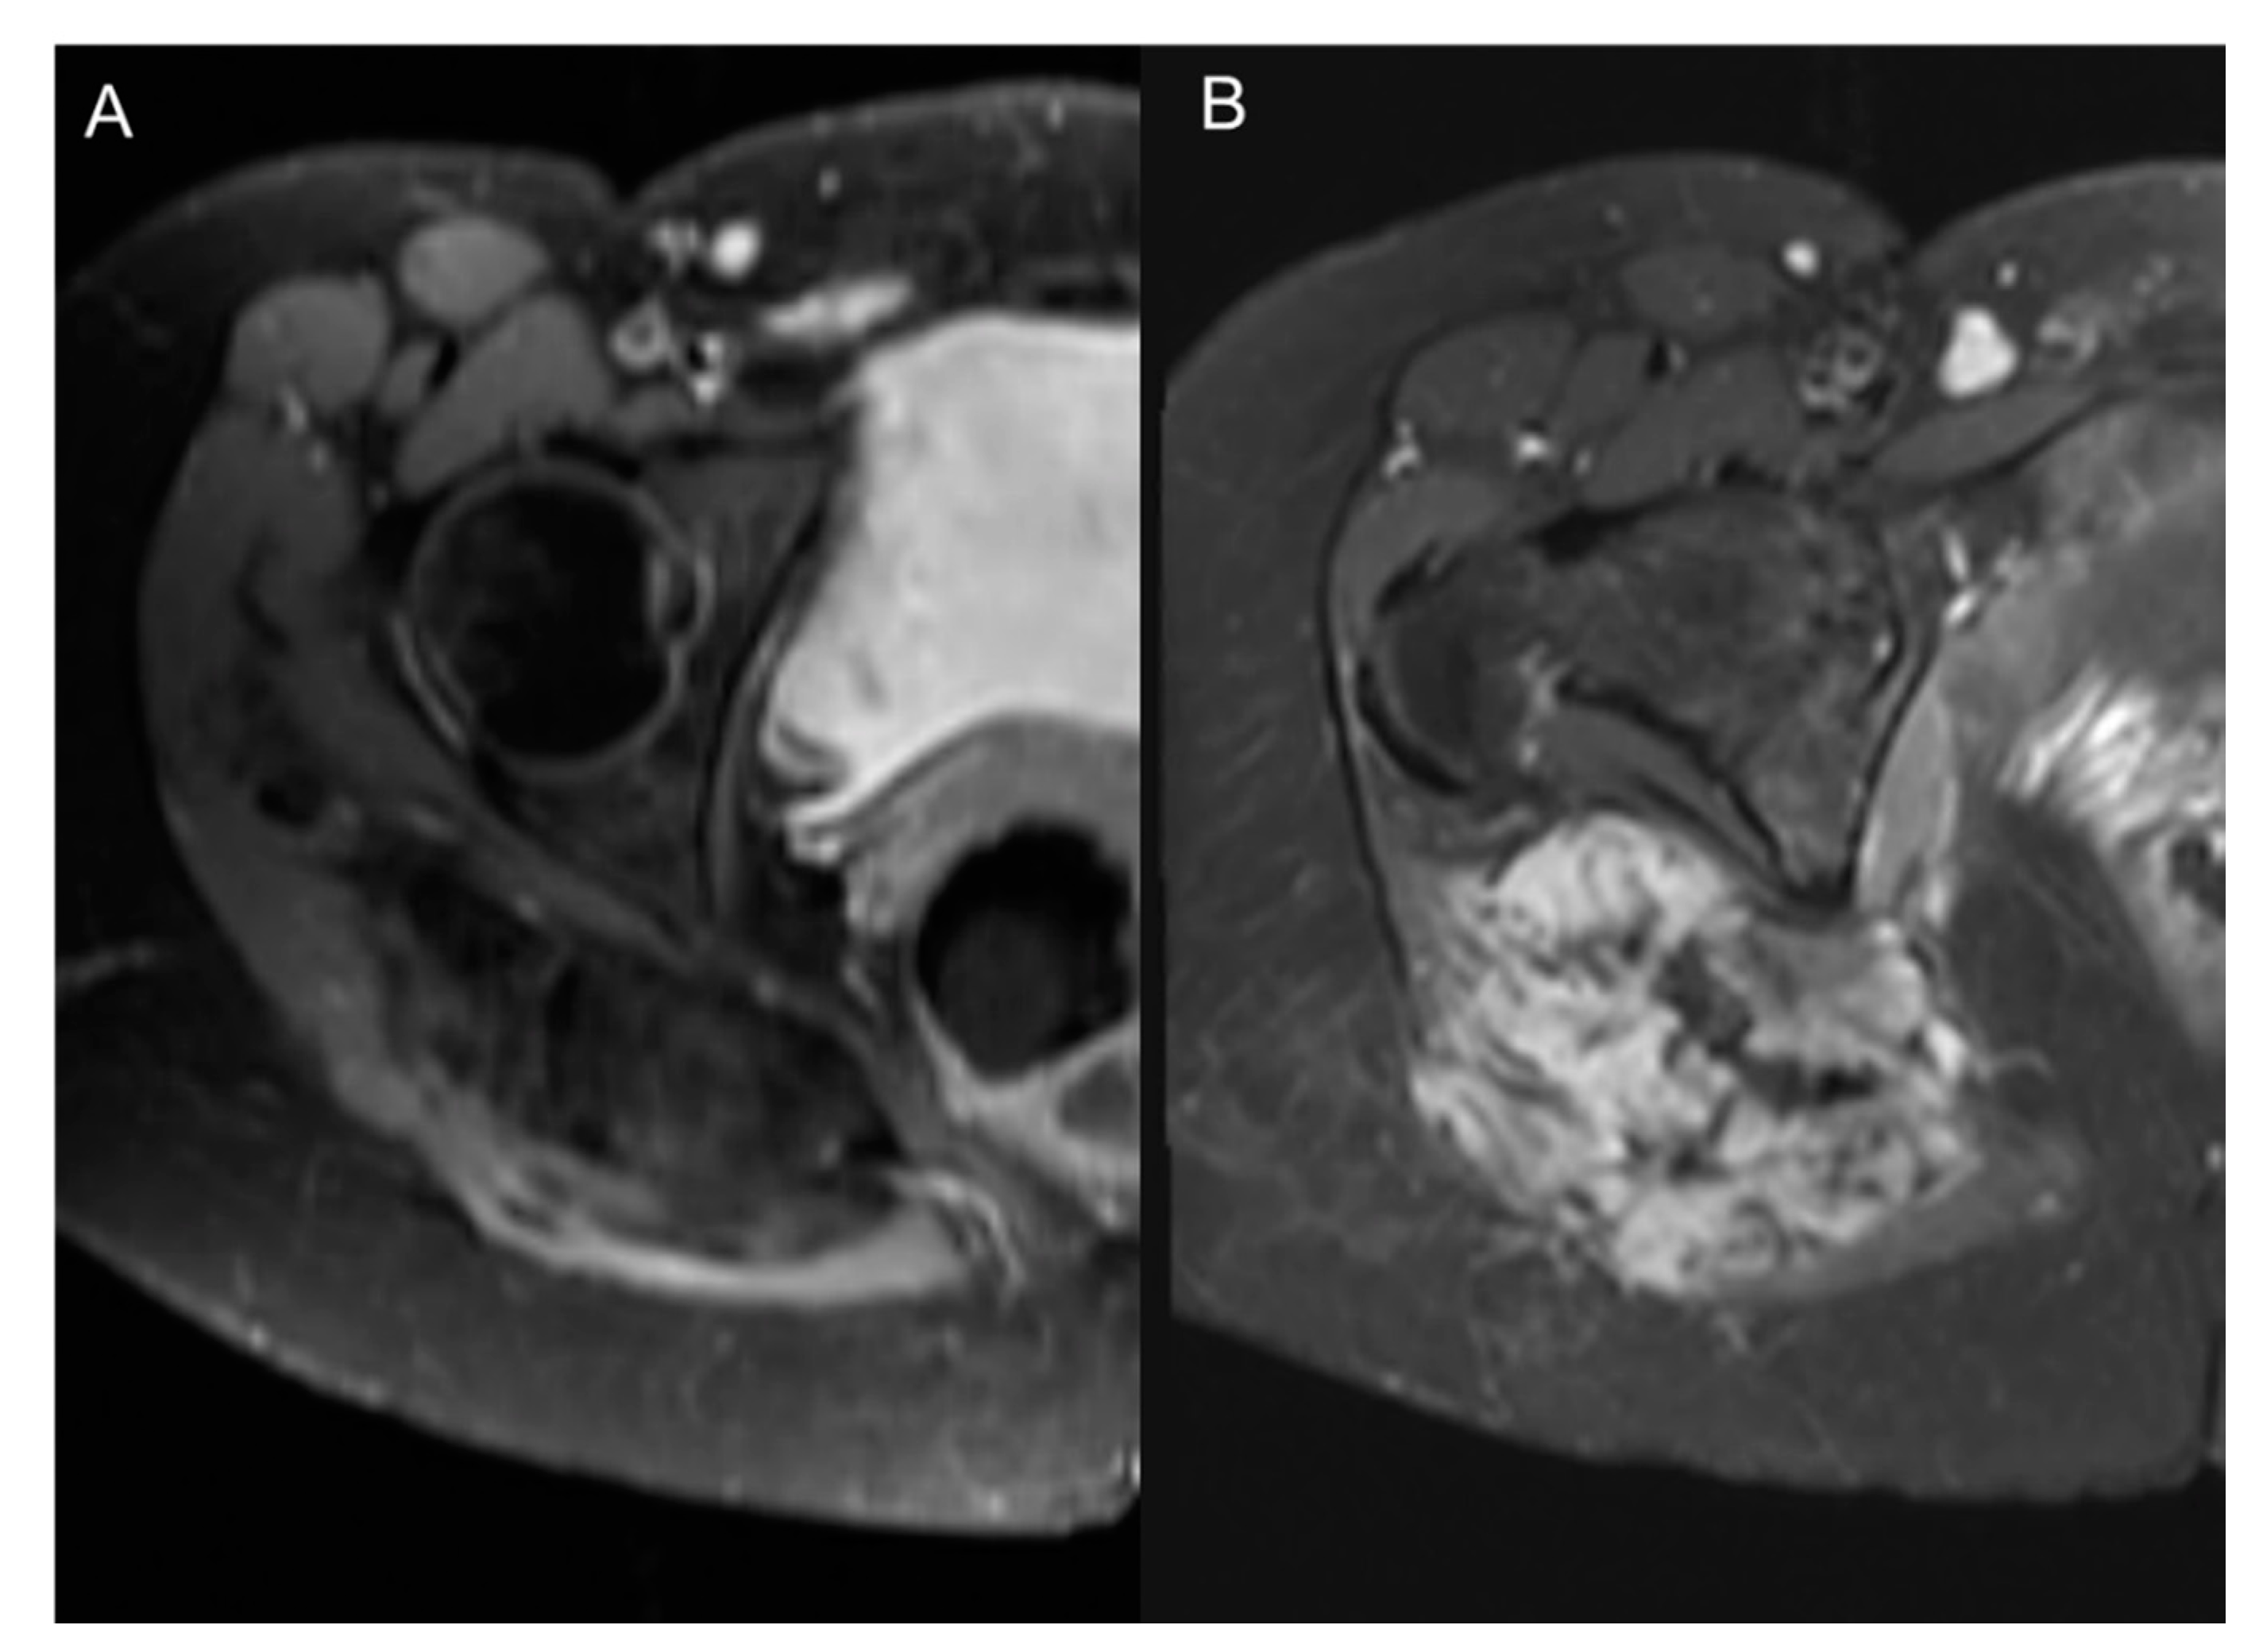

7.4. Dynamic Contrast-Enhanced Perfusion MRI

8. CT Imaging of Angiogenesis